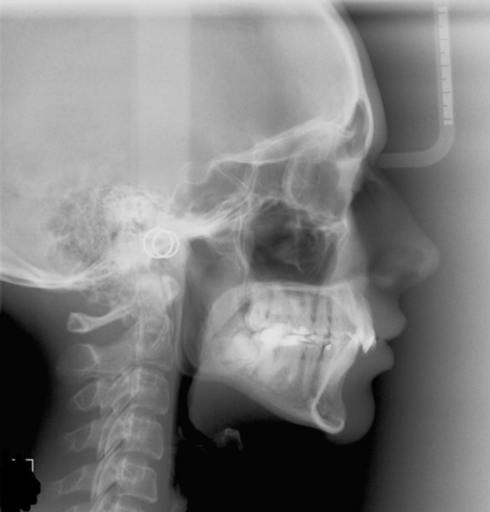

Hi I am 18 I have an underbite- I dont know how the severity of them is classed- but I know mine is not that severe- when I smile you cannot see the bottom teeth, if I try I can align the top and bottom teeth, the underbite is only prominent when my mouth is closed- it is prominent only when my mouth is closed and ESPECIALLY when I bite down- it is VERY prominent- the jaw looks massive. The distance between the top set and bottom set is slightly less than a cm. In the consultation the orthodontist said that surgery was really not necessary. The underbite can be fixed with just braces- however we had never discussed how facial aesthetics would be affected- so given I knew nothing about either treatment I couldnt assume that any difference would possibly exist and so agreed to non surgery just braces. I am starting to get an increasingly stronger feeling as I research online that there is negligable change in facial profile when you have braces only to fix the bite. Is this true? If so I am absolutely disappointed. Will the sunken "bulldog" look still be there? If so what a waste of 3 years it will have been. The way my face will look is a big deal to me. WHEN I ALIGN BOTH UPPER AND LOWER SETS OF TEETH TOGETHER THEY BOTH MANAGE TO TOUCH(just)- AND MY SIDE PROFILE LOOKS AS IF IT WOULD FOR ANY PERSON WITH NORMAL BITE. This normal side profile is what I also want- It is in my usual state(when I dont try to align) than the big jaw look is noticable. SURELY IF I CAN ACHIEVE A NORMAL LOOKING SIDE PROFILE BY ALIGNING MYSELF- AFTER 3 YEARS WHEN BRACES HAVE DONE THEIR JOB- MY SIDE PROFILE WILL BE NORMAL TOO REGARDLESS OF WHETHER IN MY USUAL STATE OR NOT? If this is the case then there is absolutely no problem and will continue with the way things are planned- if not I will try to convince my orthodontist to try surgery if it is the only way. Extra Details: I had my spacers taken off a few weeks ago and had the 4 metal things they put on the molars. So it is still early days. My next appointment is in exactly two weeks- she said the top brace would be put on first(crooked tooth is also being fixed) and later extraction when I was ready so that the actual underbite treatment could begin. I dont want to go through 3 years of this just for an imperfection to remain- If I'm going to do it especially at this age I want it to be totally fixed- even if takes a bit more pain- after all with surgery it would still take same amount of time. Thank you for reading this far- what is your opinion about the side profile- bulldog look - and what do think I should do/what should I ask her next time I see her in two weeks- I dont want her to be angry at me for wasting more time. Thanks again.